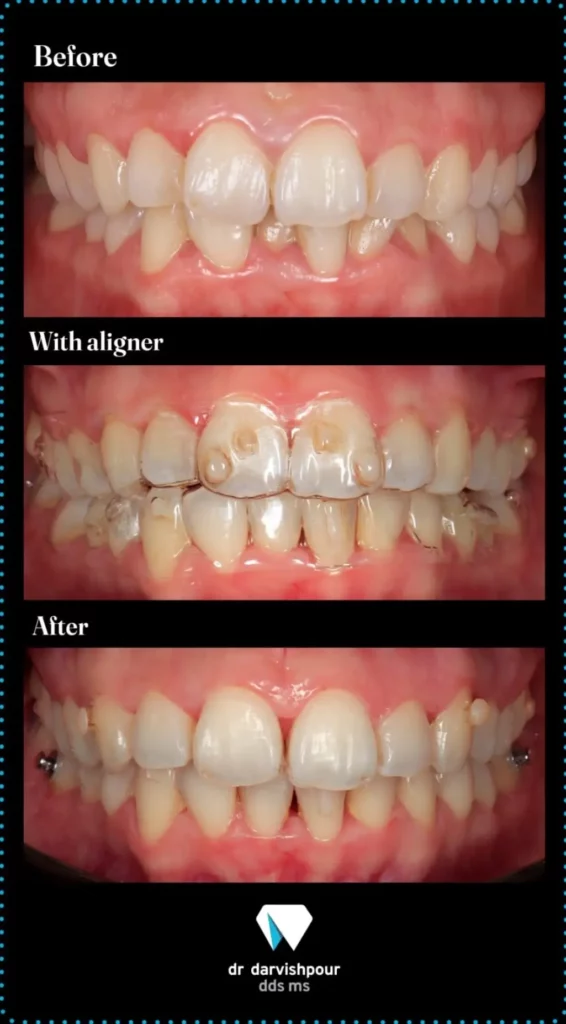

۱. دکتر هادی درویش پور – رتبه اول بورد تخصصی کشور

شاید بپرسید چرا در لیست بهترین متخصص ارتودنسی در سعادت آباد، نام پزشکی در دهکده المپیک آمده است؟ پاسخ ساده است: کیفیت مرز نمیشناسد. دکتر درویش پور دارای رتبه اول بورد تخصصی کشور هستند و همین موضوع باعث می شود که بسیاری از ساکنان سعادت آباد و شهرک غرب، ترجیح دهند با ۱۰ تا ۱۵ دقیقه رانندگی (دسترسی آسان از طریق اتوبان همت)، درمان خود را زیر نظر ایشان انجام دهند. وقتی صحبت از سلامت فک و صورت است، طی کردن مسافتی کوتاه برای رسیدن به یکی از نخبگان این رشته، منطقی ترین کار ممکن است.

دکتر درویش پور علاوه بر بورد تخصصی، در استفاده از تکنیک های نوین مانند ارتودنسی نامرئی (اینویزیلاین) پیشگام هستند. ایشان گزینه ای عالی برای کسانی هستند که به دنبال درمان های بدون سیم و پلاک های شفاف می گردند. بسیاری از مراجعین، سرعت در روند درمان و تغییرات چشمگیر در کوتاه ترین زمان ممکن را ویژگی بارز ایشان می دانند.

📽 ویدیو معرفی دکتر هادی درویش پور:

🦷 نمونه درمان ارتودنسی دکتر درویش پور: